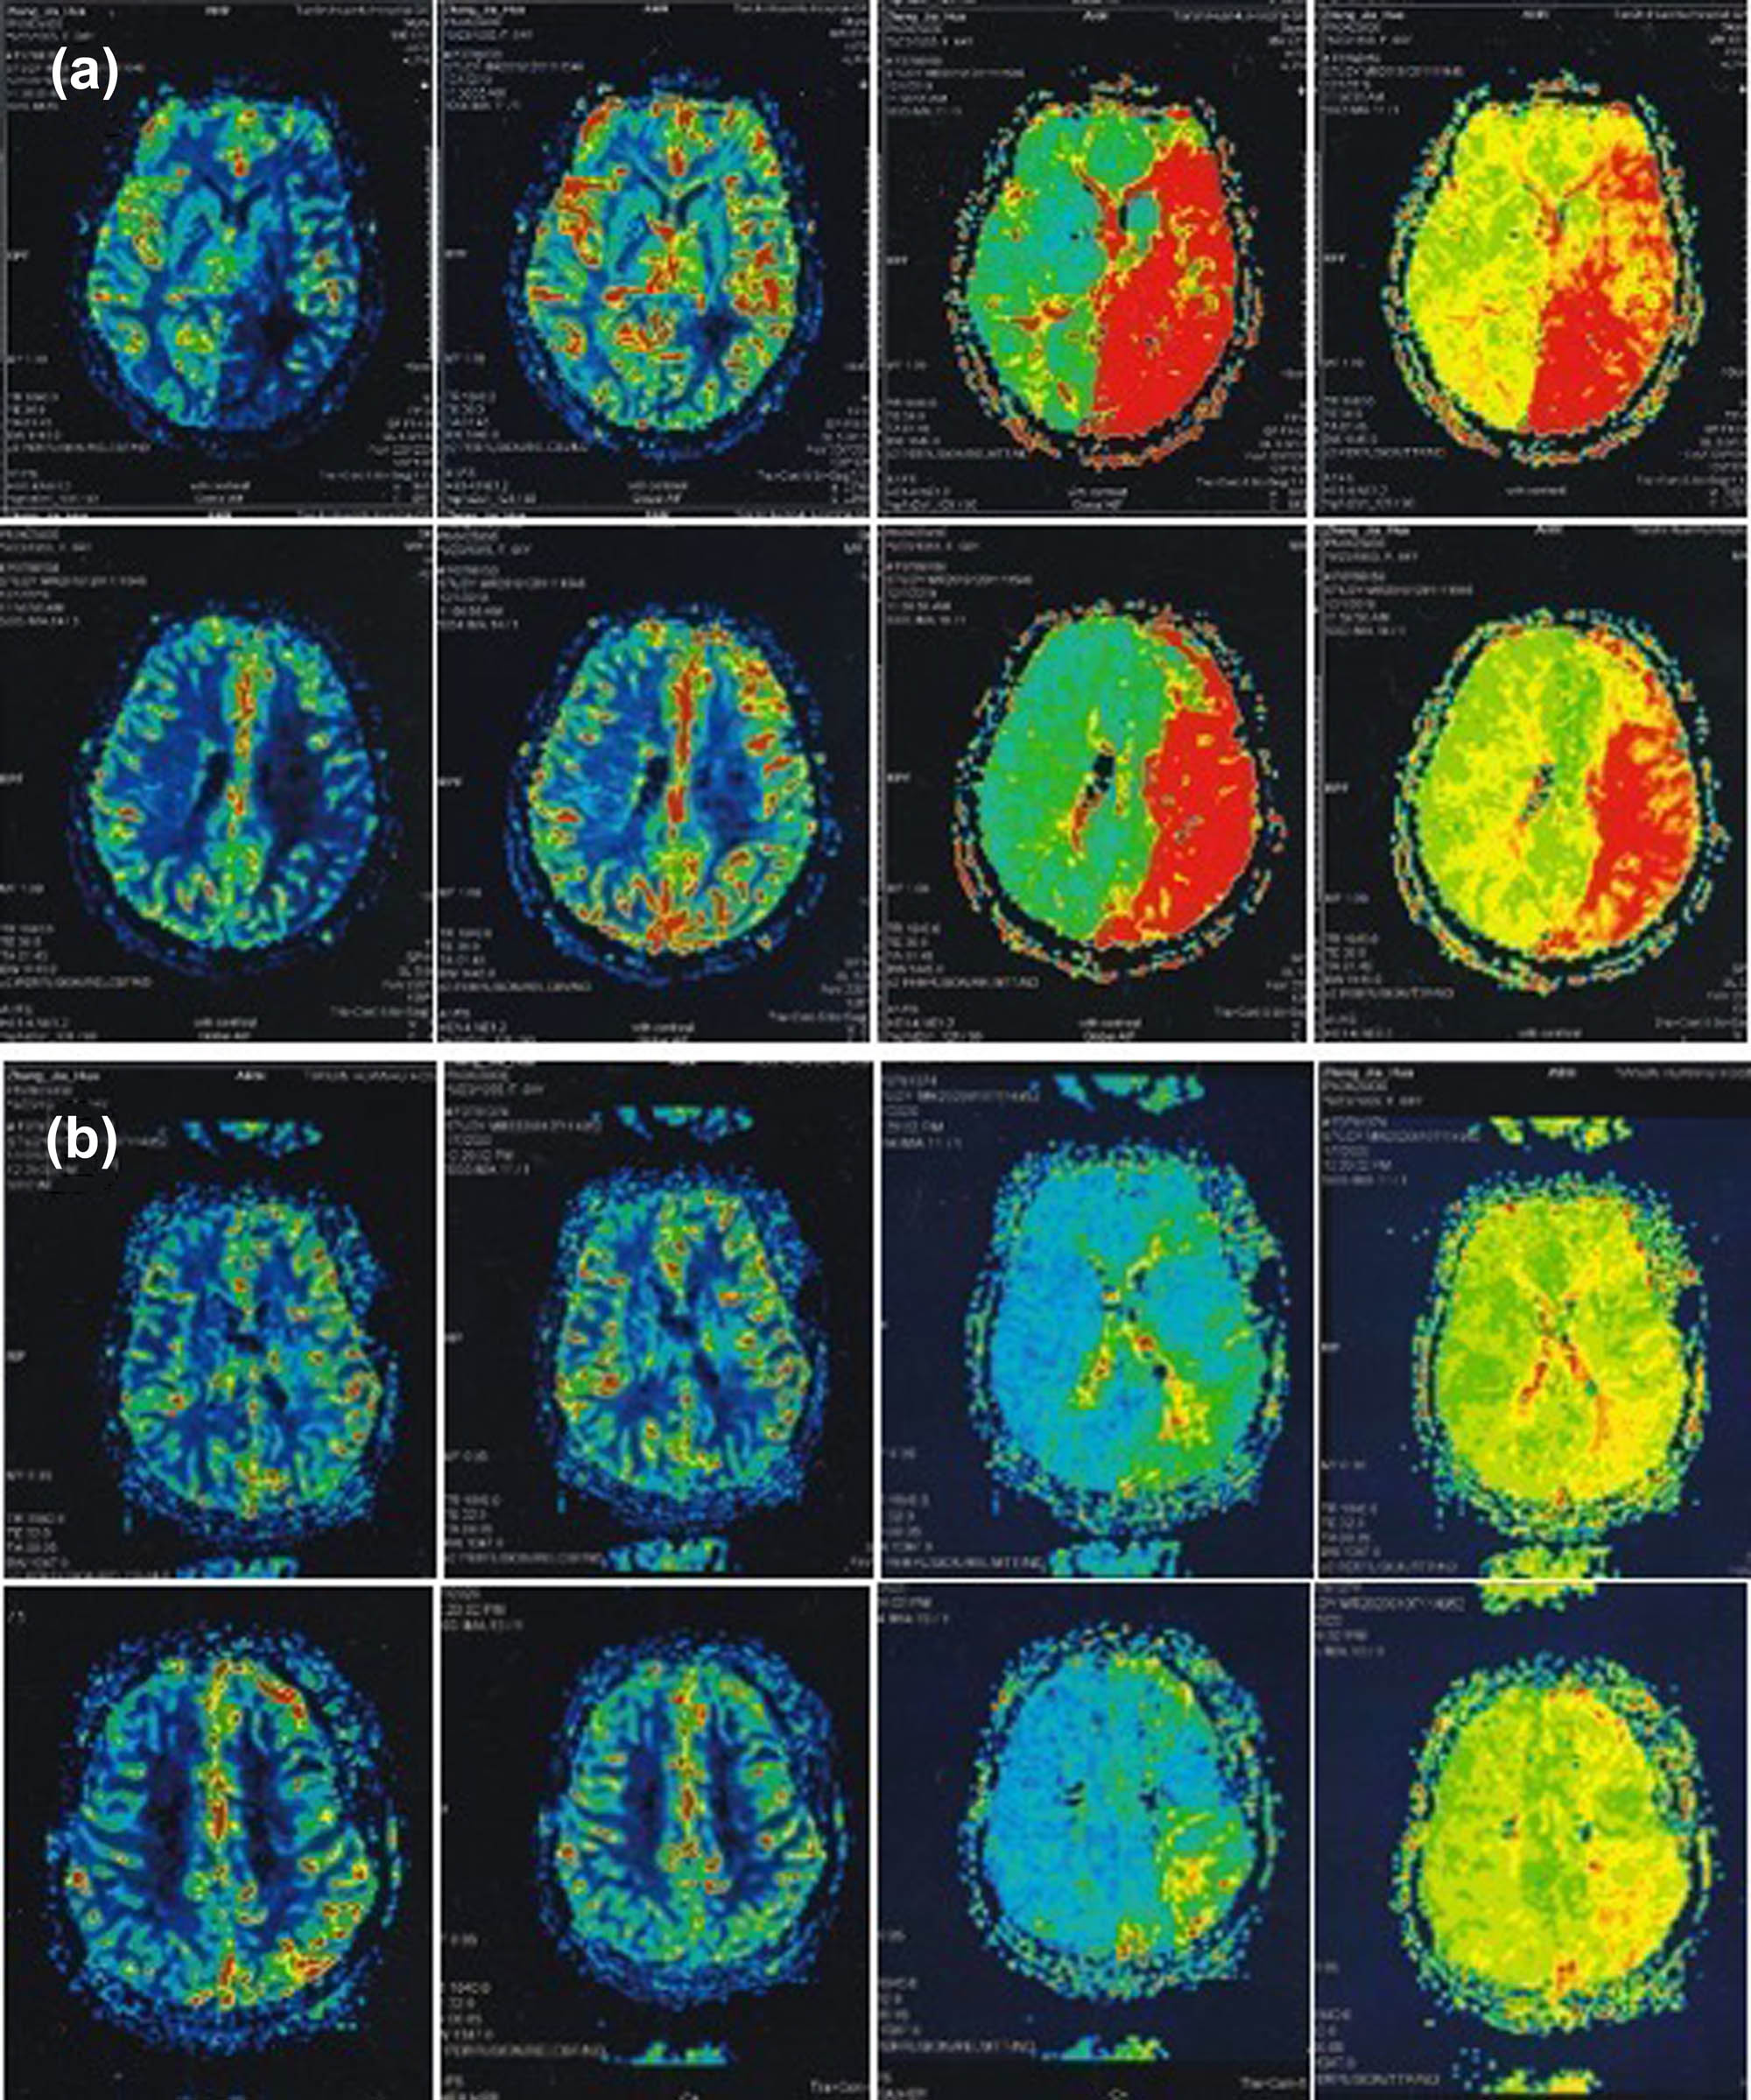

3.4 Hemodynamic changes in the operated side

Table 3 summarizes the analysis of PWI-ASPECTS score data before and after bypass surgery. Postoperative DSC-PWI showed hemodynamic improvement in all 12 patients (Figure 4). The CBF-ASPECTS increased from 5.00 [5.00; 6.00] to 8.00 [8.00; 9.00], the MTT-ASPECTS increased from 2.00 [2.00; 3.00] to 7.00 [6.00; 8.00] and TTP-ASPECTS increased from 3.00 [3.00; 3.00] to 6.00 [5.00; 8.00] postoperatively, with a statistically significant difference. However, the CBV-ASPECTS did not significantly differ before and after the bypass surgery. These changes in PWI-ASPECTS score parameters after direct hematopoietic reconstruction suggest that significant improvements in cerebral perfusion in the surgical hemisphere can be expected after surgery. The patients with lower preoperative PWI-ASPECTS score have more significantly improved postoperative cerebral perfusion.

A 64-year-old woman with recurrent ischemic stroke. Cerebral perfusion imaging before (a) and after (b) STA–MCA double bypass.